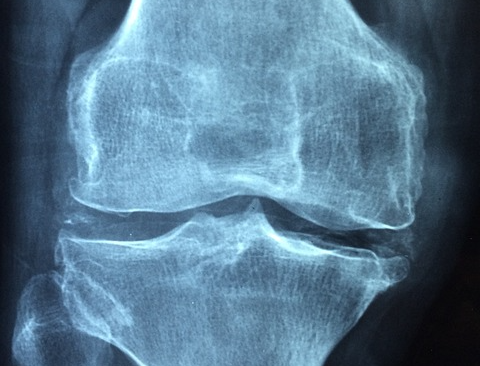

✅ 골다공증은 뼛속에 구멍이 많이 생긴다는 뜻이며, 이는 뼈를 약화시켜 뼈를 연약하게 만들고 골절에 취약하게 만듭니다. 이 질환은 특히 폐경 후 노년층, 특히 여성에게 널리 퍼져 있습니다. 골다공증은 노화의 불가피한 부분처럼 보일 수 있지만 올바른 지식과 생활 습관을 통해 관리하고 예방할 수 있습니다. 이 블로그에서는 골다공증의 증상, 원인 및 위험 요인, 예방 전략을 자세히 살펴봄으로써 뼈 건강에 대한 올바른 지식을 이해하고, 생활 속 적절한 운동과 음식섭취로 뼈건강 유지에 도움이 되길 바랍니다.

✅ 골다공증은 골절이 발생할 때까지 눈에 띄는 증상 없이 진행되기 때문에 흔히 '침묵의 질병'이라고 불립니다. 골다공증과 관련된 가장 흔한 골절은 엉덩이, 척추, 손목에 나타납니다. 주의해야 할 초기 징후는 다음과 같습니다.

이러한 증상은 다른 질환과 겹칠 수 있으므로 이러한 증상이 나타나면 의학적 조언을 구하는 것이 중요합니다. 골밀도 검사(DEXA 스캔)는 골다공증을 진단하고 골절 위험을 평가하는 신뢰할 수 있는 방법입니다.